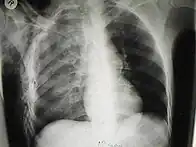

Scanner abdominal (rayons X) d'un patient présentant un emphysème sous-cutané (flèché) | |

Les cas importants d'emphysème sous-cutané sont faciles à diagnostiquer en raison des signes caractéristiques de l'affection. Dans certains cas, les signes sont subtils, ce qui rend le diagnostic plus difficile. L'imagerie médicale est utilisée pour diagnostiquer la maladie ou confirmer un diagnostic établi à l'aide de signes cliniques. Sur une radiographie du thorax, l'emphysème sous-cutané peut être vu comme des stries radiotransparentes dans le modèle attendu du groupe de muscles principaux du pectoral. L'air présent dans les tissus sous-cutanés peut interférer avec la radiographie du thorax, ce qui peut masquer des affections graves comme le pneumothorax. Elle peut également réduire l'efficacité de l'échographie thoracique. D'autre part, comme l'emphysème sous-cutané peut être visible sur les radiographies du thorax avant un pneumothorax, sa présence peut être utilisée pour déduire celle de cette dernière lésion. L'emphysème sous-cutané peut également être observé sur les scanners, les poches d'air apparaissant comme des zones sombres. Le scanner est si sensible qu'il permet généralement de trouver l'endroit exact d'où l'air pénètre dans les tissus mous. En 1994, M. T. Macklin et C. C. Macklin ont publié d'autres aperçus sur la physiopathologie du syndrome de Macklin spontané survenant à la suite d'une grave crise d'asthme. La présence d'un emphysème sous-cutané chez une personne qui semble très malade et fébrile après une crise de vomissements suivie d'une douleur thoracique gauche est très évocatrice du diagnostic du syndrome de Boerhaave, qui est une urgence vitale causée par une rupture de l'œsophage distal. L'emphysème sous-cutané peut être une complication de l'insufflation de CO2 avec la chirurgie laparoscopique. Une augmentation soudaine du CO2 en fin de marée après la hausse initiale qui se produit avec l'insufflation (les 15-30 premières minutes) devrait faire suspecter un emphysème sous-cutané. Il est à noter que l'oxymétrie de pouls et la pression des voies aériennes ne varient pas dans l'emphysème sous-cutané, contrairement à l'intubation endobronchique, au capnothorax, au pneumothorax ou à l'embolie au CO2.